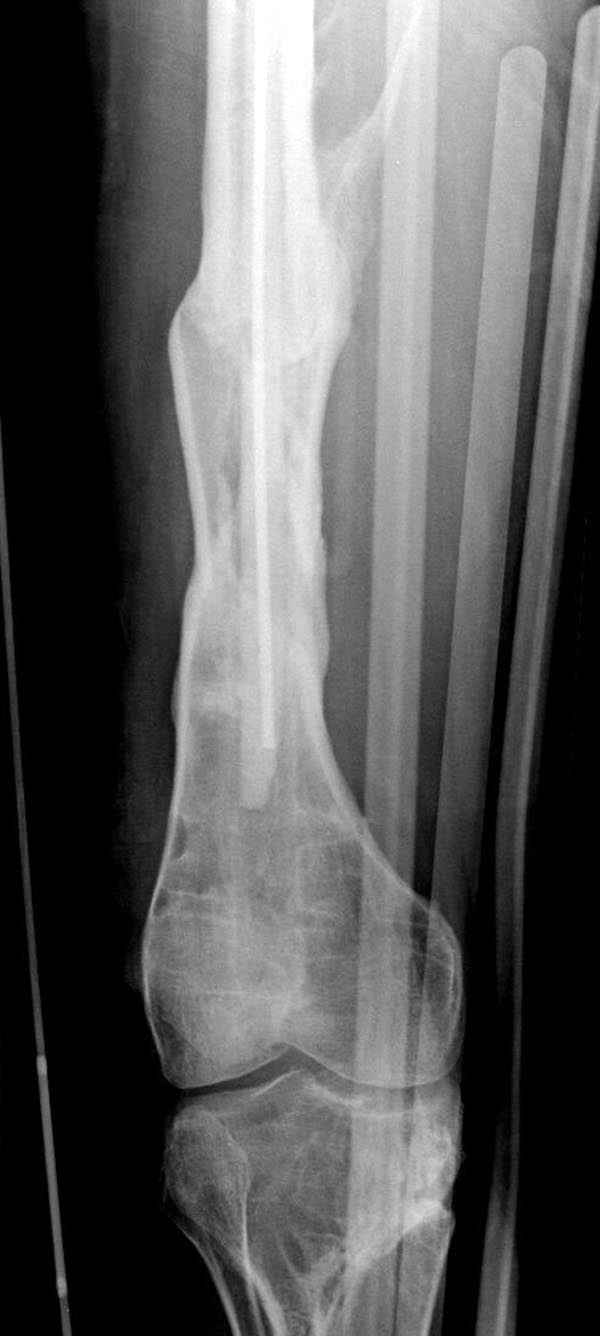

если первые 4 месяца послеоперационного периода проходил без проблем, но на 5 месяце появились боли в дистальном отделе бедра и температура, т.е. симптомы медуллярного инфицирования (рис №3, №4).

Замена реконструктивного штифта “Custom made Nail” с антибиотиком (рис №5, №6),

после промывки канала с рассверливанием внутреннего кортекса, через 4 недели антибиотический штифт удалили, оспалителный процесс остановлен и бедро сросся.

Мы не дождались “Happy End”, у больного IQ в пределах 70%, через 6 месяцев вернулся после небольшой травмы, споткнувшись получил перелом

того же бедра (рис №7).